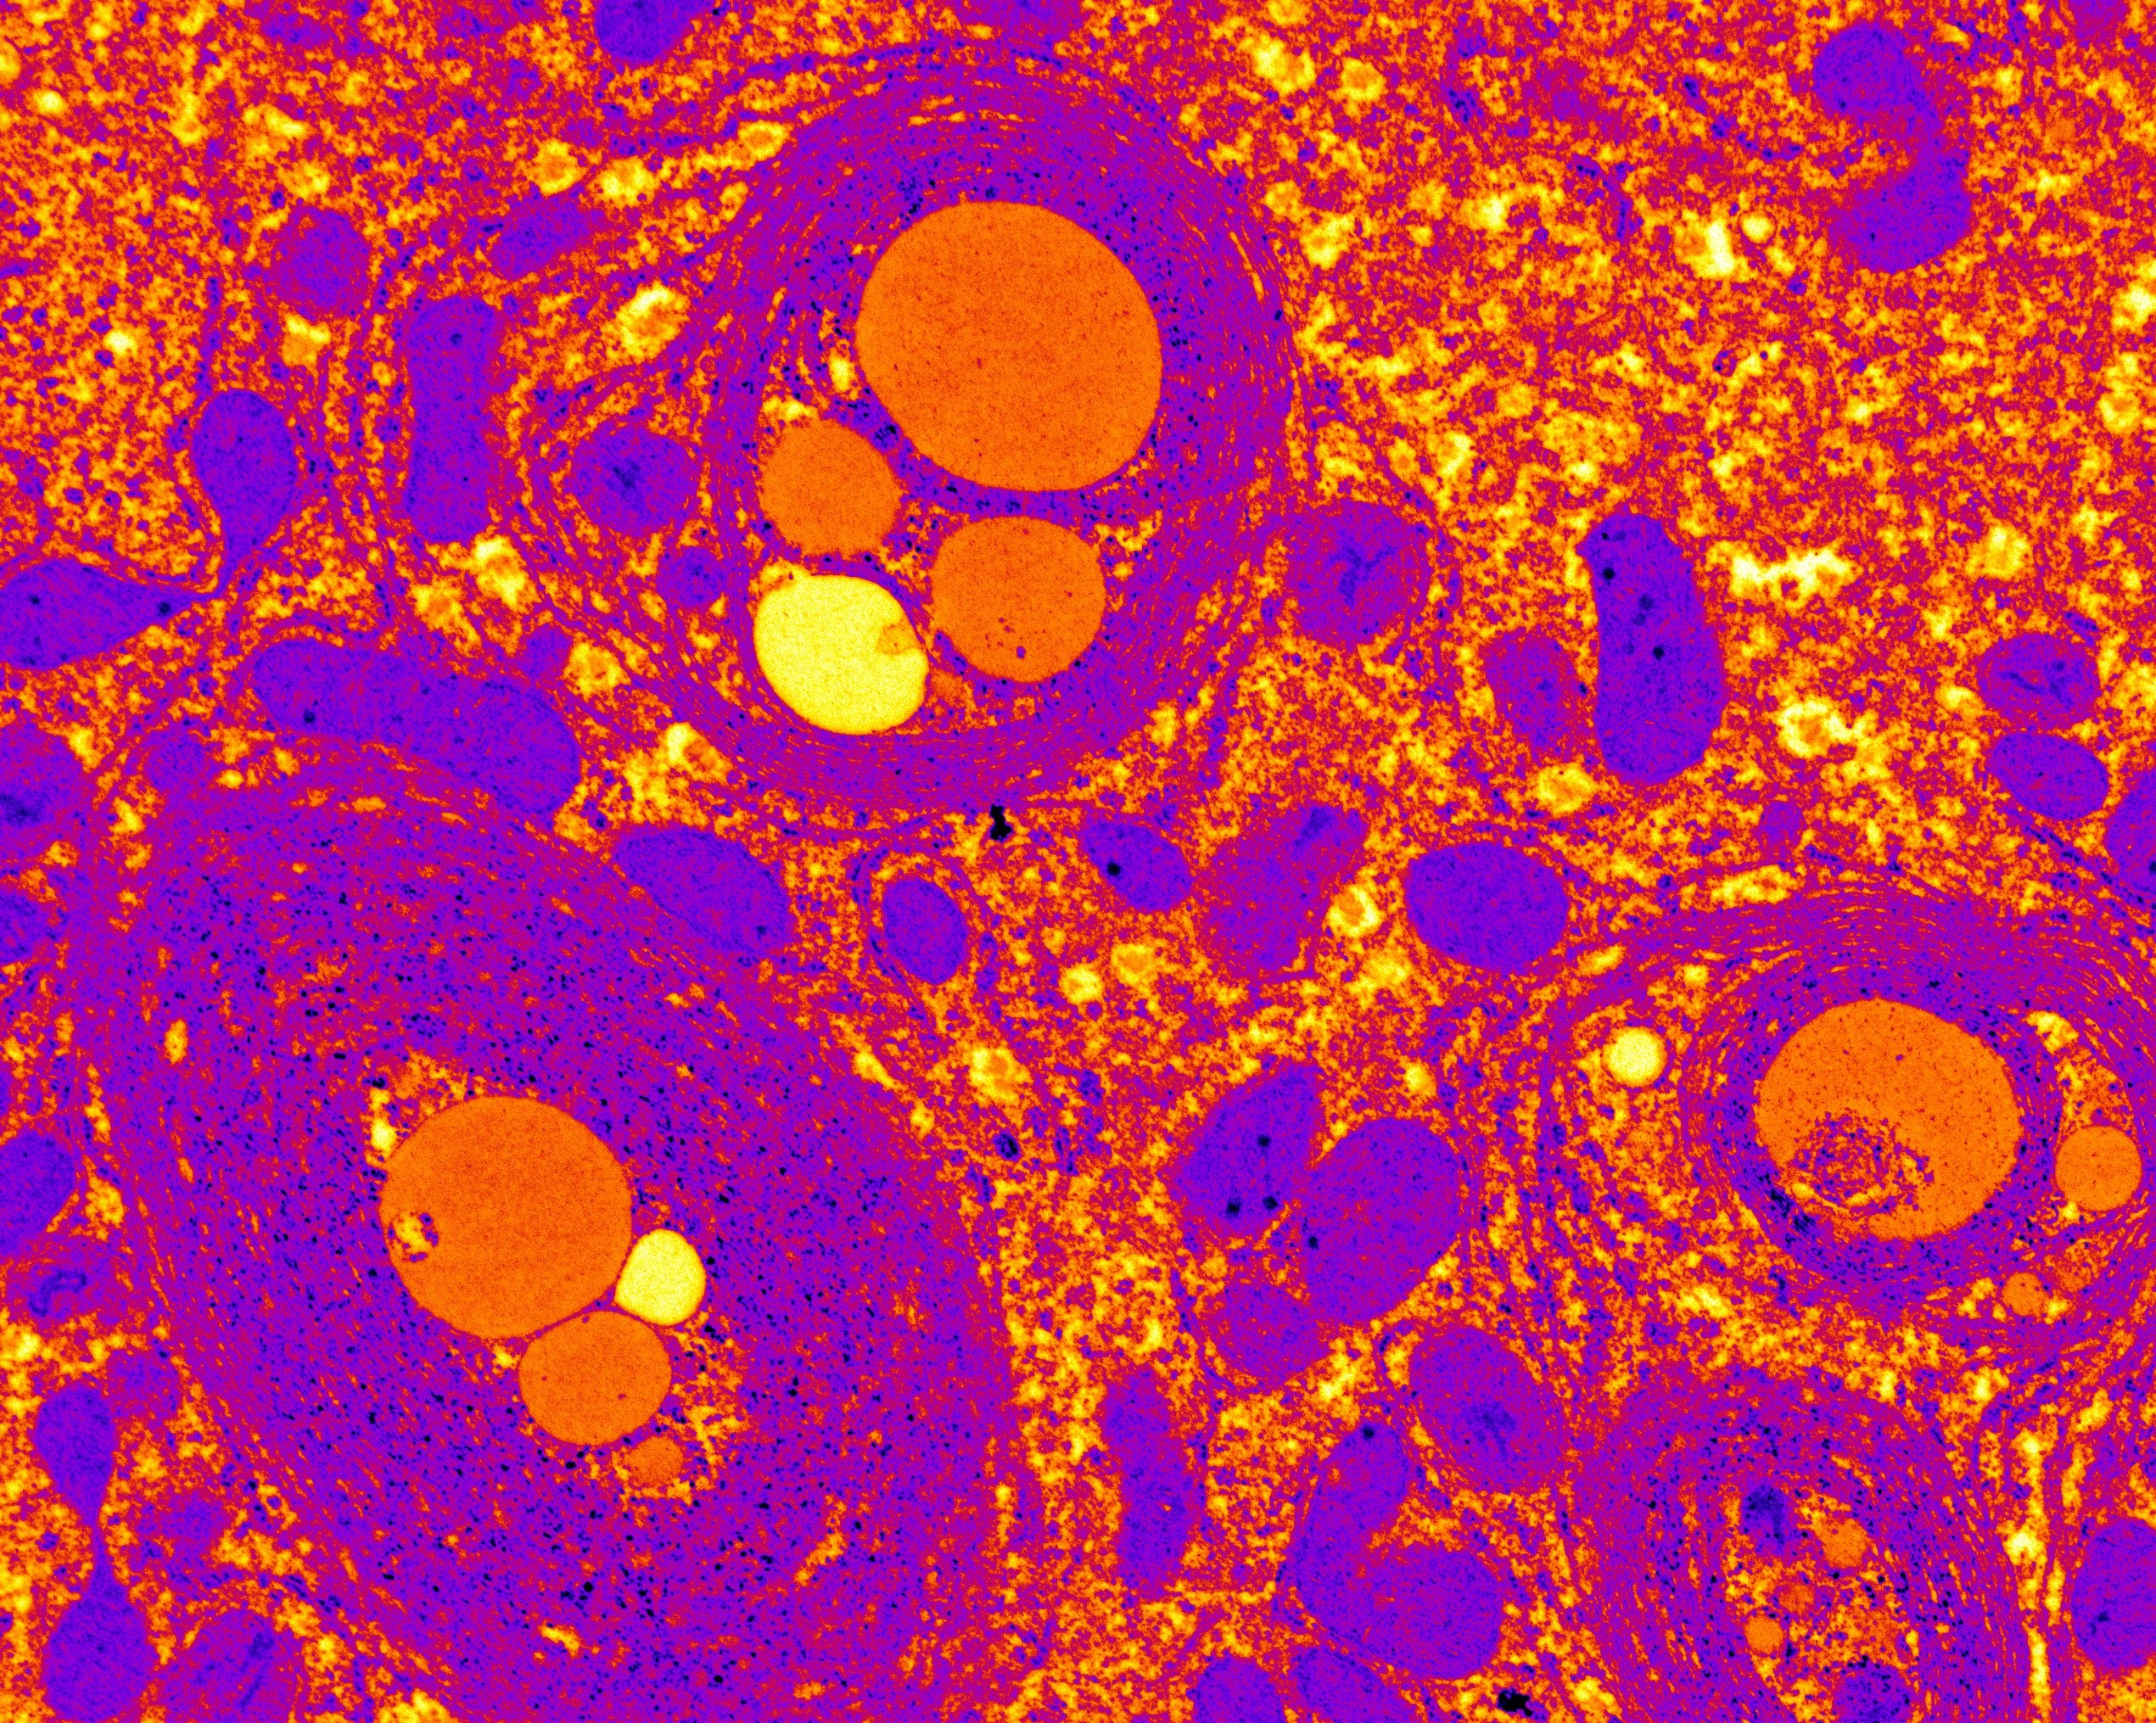

Descubierto un nuevo mecanismo para atenuar los efectos de la enfermedad de hígado graso